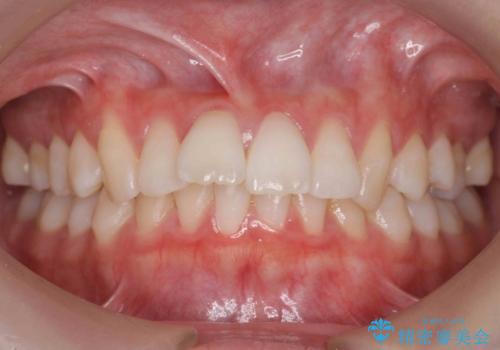

[ インビザライン ] 目立たないマウスピース矯正で、前歯のがたつきをきれいにしたい

担当医 大元洋佑

![[ インビザライン ] 目立たないマウスピース矯正で、前歯のがたつきをきれいにしたいの症例 治療前](https://seimitsushinbi.jp/wp/wp-content/uploads/2024/04/IMG_3912-500x350.jpg?v=1711960039)

![[ インビザライン ] 目立たないマウスピース矯正で、前歯のがたつきをきれいにしたいの症例 治療後](https://seimitsushinbi.jp/wp/wp-content/uploads/2024/04/cd64e6566cc0683feee2abf20f8241f9-500x350.jpg?v=1711960118)